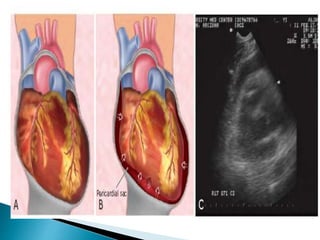

** Cardiac tamponade

 The classic clinical triad of

◦ Muffled heart sounds

◦ Hypotension

◦ Distended veins

 Focused assessment with sonography for

trauma (FAST) is a rapid and accurate

method of imaging the heart and

pericardium that can effectively identify

cardiac tamponade.

 Treatment subxiphoid pericardiocentesis

** Cardiac tamponade The classic clinical triad of ◦ Muffled heart sounds ◦ Hypotension ◦ Distended veins  Focused assessment with sonography for trauma (FAST) is a rapid and accurate method of imaging the heart and pericardium that can effectively identify cardiac tamponade.  Treatment subxiphoid pericardiocentesis